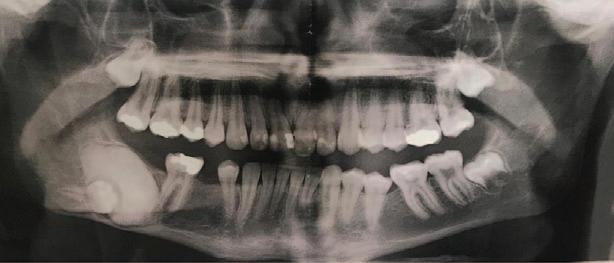

A 30-year-old patient presented to your clinic complaining of a discoloured front tooth (Figures 1 and 2). There was no pain or other symptoms associated with it and it has become increasingly discoloured over time.

1. What is the likely reason for this type of discolouration?

2. What special tests do you perform as part of your exam?

3. What are the potential sequalae for this tooth?

4. What are the possible treatment options for

this tooth and what are the potential difficulties with doing a root canal treatment?

Answers on page 45.

FIGURE 1: Patient presenting with discoloured front tooth. FIGURE 2: Periapical radiograph 1.